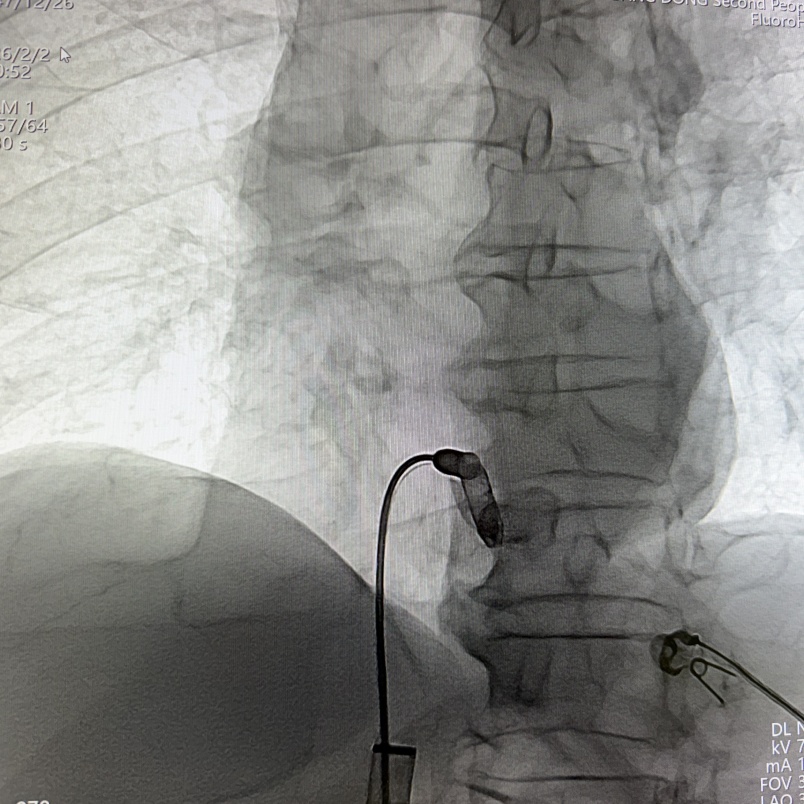

RAO 30°体位下,缓慢推送导管,直至保护套筒位于右心耳底部,使用解剖标记/猪尾导管造影确定右心耳的部位和右心耳的深度,当观察到“雨刷”摆动后停止推进;在透视下解锁保护套筒,保持起搏器不动,完全回撤保护套筒,观察到头端螺旋没有位移,且导管形态张力合适。

工程师进行定位标测(腔内图形、损伤、阻抗、感知、阈值),参数正常。在旋入固定之前,留存影像来记录机器“V形标记”的起始位置,缓慢顺时针旋转控制旋钮,旋入AVEIR™ AR器械过程中持续测试观察趋势,旋至1.5圈,进入对接栓模式;进行张力测试,整体轻微施加张力回撤导管,持续几个心动周期后将无导线起搏器返回松弛状态进行电学参数测试,参数稳定,完成心房无导线心脏起搏器植入。